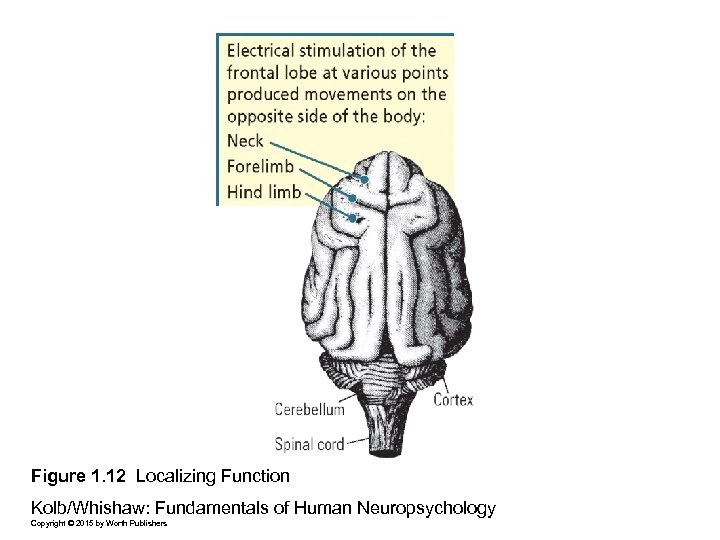

Figure 1. 12 Localizing Function Kolb/Whishaw: Fundamentals of Human Neuropsychology Copyright © 2015 by Worth Publishers